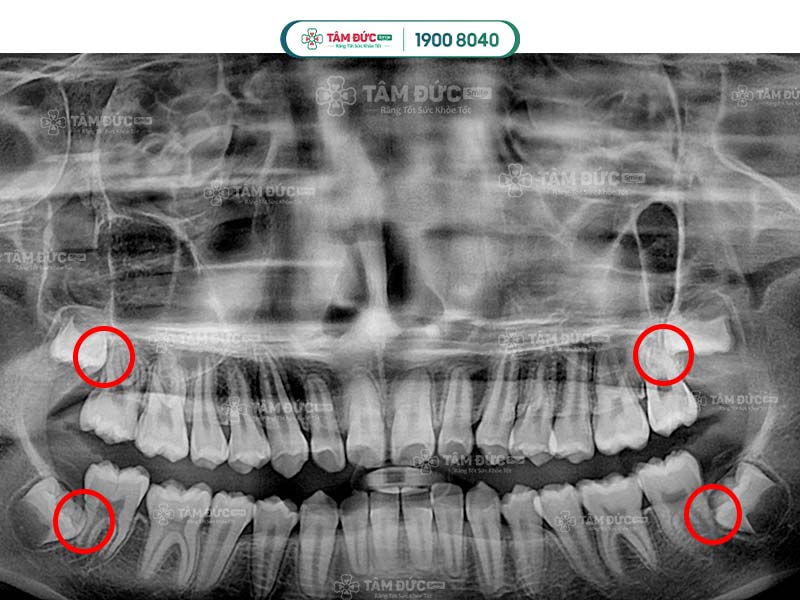

1. Những đặc điểm của răng khôn mọc lệch 45 độ

Dấu hiệu nhận biết Quý khách có răng khôn mọc lệch 45 độ là các cơn đau âm ỉ, kéo dài nhiều ngày. Nguyên nhân là vì khoảng trống trên hàm đã không còn nhiều, vị trí của răng khôn bị ảnh hưởng bởi mô mềm và răng hàm số 7. Điều này đã làm răng mọc nghiêng theo nhiều góc độ so với răng số 7 như 45 độ hay 90 độ.

Răng khôn mọc lệch làm ảnh hưởng răng số 7

Bước 2: Đối với răng khôn mọc lệch, Quý khách cần được chụp X-Quang để xác định hướng mọc, vị trí của chân răng, xương hàm và dây thần kinh.